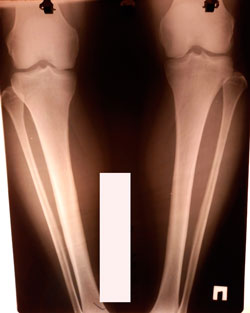

Дата операции - 28.01.2021

Исходник - 44 года.

перед крутками